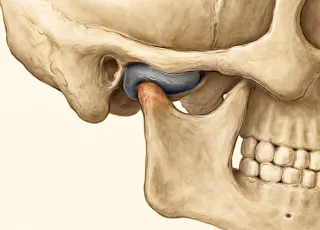

Причины развития патологий разнообразны — от воспалительных изменений до аутоиммунных болезней. Требуется целый комплекс диагностических мероприятий для постановки диагноза. Одним из наиболее информативных методов является магнитно-резонансная томография. МРТ позволяет визуализировать детальное анатомическое строение, что значительно ускоряет диагностический поиск.

Томография позволит выявить воспалительные и инфекционные процессы, повреждение костных структур или связочного аппарата, наличие патологической жидкости в суставной капсуле, дегенеративные болезни, опухоли. Для повышения диагностической мощности исследования врач может прибегнуть к применению контрастного вещества.